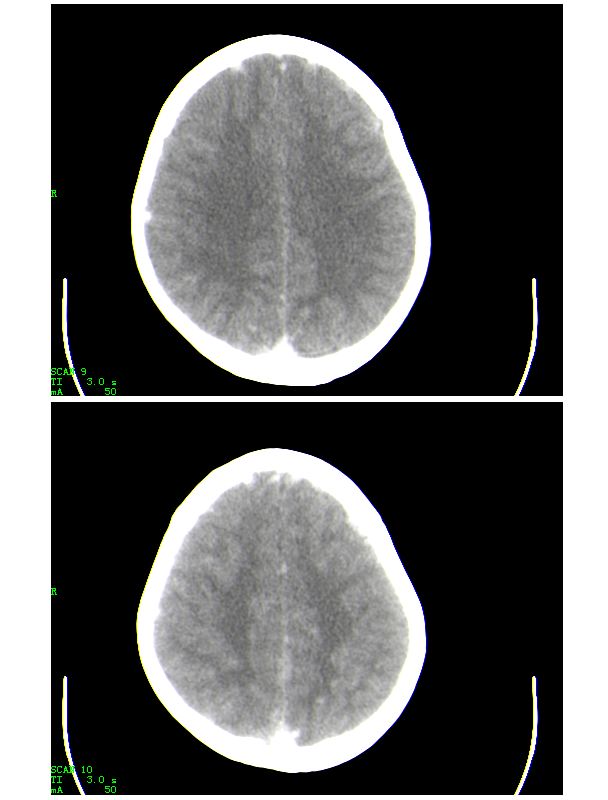

男,13岁,头部外伤后头痛、呕吐三小时就诊,查体,见小孩精神状态尚可,面部,嘴唇青紫明显,后作心脏彩超证实为“发四”,有复查片,大家先看看首诊片,考虑什么

感谢大家的关注,本例我们最后诊断为高血红蛋白症所致的脑血管改变,患者血红蛋白258g/l

下面是第二天的复查和受伤后第五天的复查,左侧硬膜下血肿有所吸收,脑内条状高密度无改变